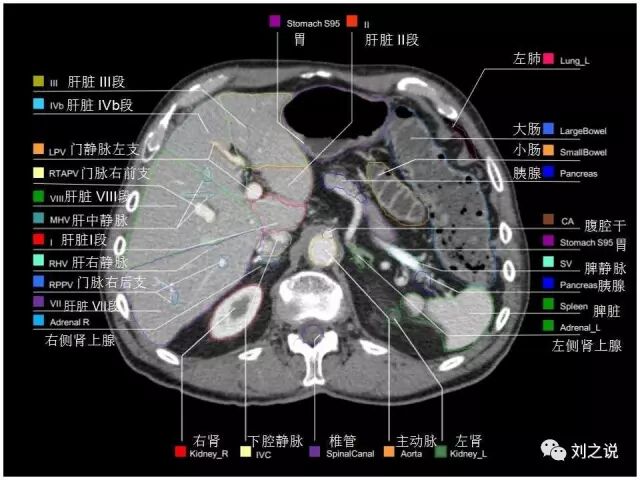

【解剖】高清实用 腹部CT断层

参考RTOG共识和3D-body解剖。

来源:刘之说